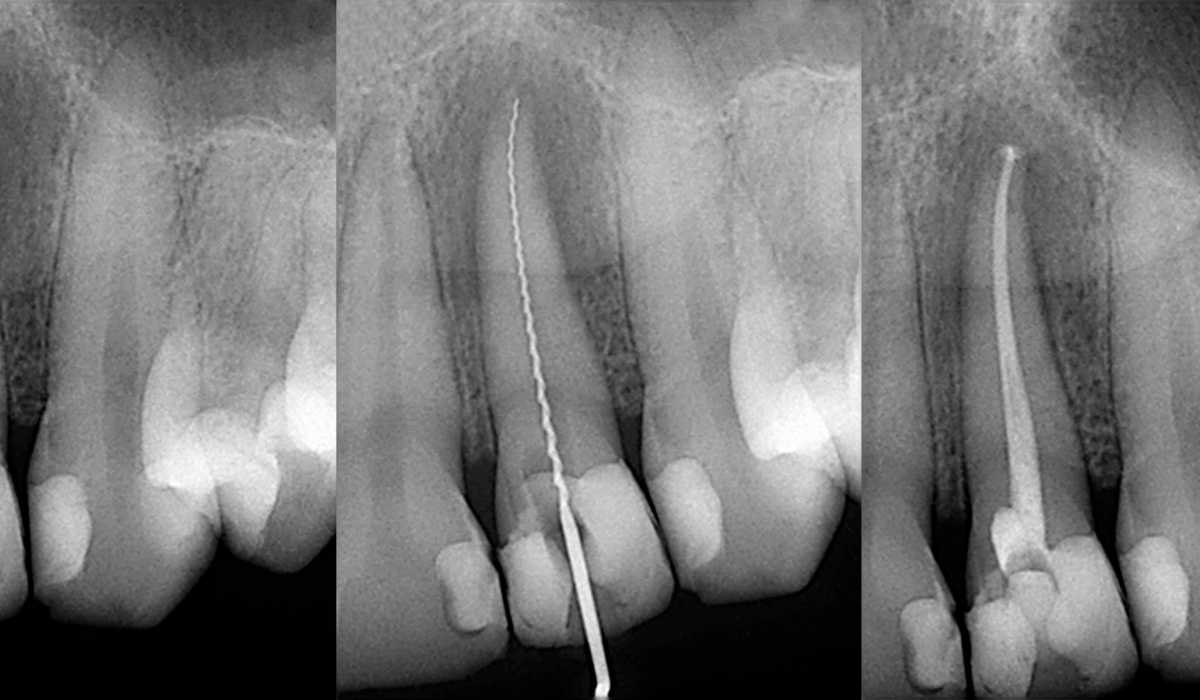

فایلهای دندانپزشکی جز مهم ترین ابزار های دندانپزشکی هستند. این ابزارها کاربرد و اهمیت زیادی در ترمیم های کانال ریشه دندان برای تمیز کردن و شکل دادن به کانال ریشه مورد استفاده قرار می گیرد. این فایل ها به برداشتن بافت عفونی، صاف کردن دیواره های کانال و آماده سازی کانال ها برای پر شدن کمک می کنند. تنوع در فایل های دندانپزشکی امکان درمان دقیق و موثر را فراهم می کند. درک انواع و کد رنگ آنها را برای متخصصان دندانپزشکی ضروری است و به آنها در انتخاب فایل مناسب کمک می کند.

فایل های دستی که جز ابزار های دندانپزشکی هستند که به صورت دستی مورد استفاده قرار می گیرد. این فایل ها بازخورد لمسی ارائه می دهند به این معنی که پزشک از طریق حس لامسه ی خود برای پاکسازی و شکل دادن به کانال ریشه ی دندان استفاده می کند. این فایل ها به دندانپزشکان اجازه می دهند شکل و مقاومت کانال را احساس کنند. با استفاده از این ابزار دندانپزشکان می توانند متناسب با ساختار کانال و زاویه آن ترمیم مورد نظر خود را انجام داده و کانال را برای استفاده از فایل روتاری آماده کنند. از انواع فایل های دستی می توان به موارد زیر اشاره کرد:

K فایل که جز قدیمی ترین فایل های اندو هستند. ابزارهای پیچ خورده ای شکل هستند که به دلیل انعطاف پذیری و استحکام بالای خود در برابر شکستن شناخته شده اند. از این فایل ها برای ترمیم کانال های منحنی استفاده می شوند و دارای سطح مقطع مربع شکل هستند.

H فایل یا فایلهای Hedström به دلیل لبههای مارپیچی و بسیار تیزی که دارند میزان برش تهاجمیتری (سرعت کار بیشتر) دارند. از این فایل ها برای خارج کردن بافت های آسیب دیده، عفونت و یا گوتا پرکا از کانال ریشه استفاده می شود. این فایل ها انعطاف پذیری و مقاومت کمتری نسبت به K-Files دارند.